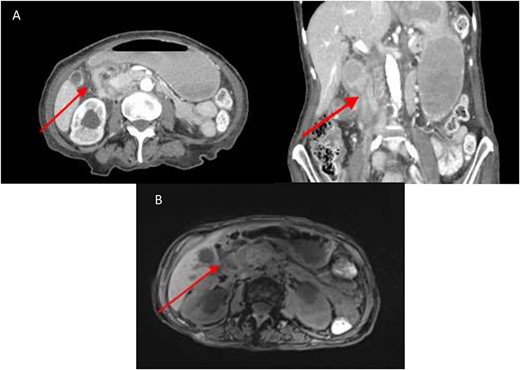

An abdominal computed tomography (CT) performed at this admission demonstrated soft tissue thickening around the second part of duodenum (D2), suggestive of a possible malignant stricture (Fig. 1A). Magnetic resonance imaging (MRI) showed an area of retroperitoneal soft tissue paralleling D2 resulting in extrinsic compression (Fig. 1B).

(A) CT abdomen showing marked luminal narrowing (red arrow) at the second part of the duodenum (axial and coronal section). (B). T1 MRI Showing retroperitoneal soft tissue (red arrow) paralleling the second part of duodenum resulting in extrinsic compression.